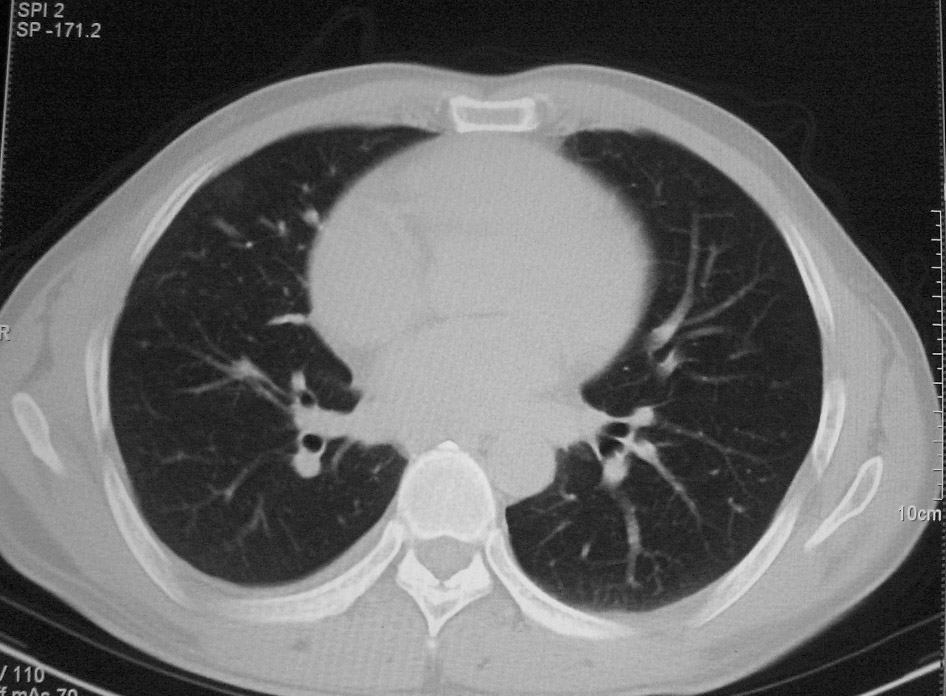

标题: CT5485:[原创]肺部占位请讨论

右肺上叶中央型肺癌并上叶肺不张、纵隔淋巴结肿大

右上叶支气管后壁明显增厚,支持右肺上叶中央型肺癌伴右上叶肺不张、纵隔淋巴结肿大。

右上叶支气管后壁明显增厚,支持右肺上叶中央型肺癌伴右上叶肺不张、纵隔淋巴结肿大。建议支气管镜检查。

右上叶支气管开口变窄,纵隔见肿大的淋巴结。支持右上叶中心型肺癌并右上叶不张纵隔淋巴结肿大。

右肺上叶中央型肺癌并上叶肺不张、纵隔淋巴结肿大.右侧少量胸腔积液。

右上肺中心型肺癌并肺不张,纵膈淋巴结肿大。右侧少量胸腔积液。